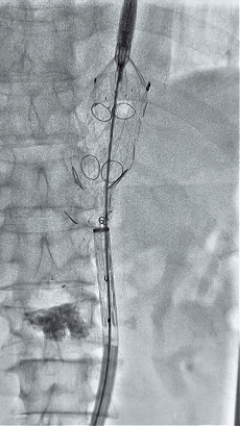

3. 经右股动脉导入超硬导丝,然后导入先健G-Branch 胸腹主动脉主体覆膜支架TAAA3418120e7i1010 一枚,释放主体支架至内分支打开,然后经左侧肱动脉入路,抓捕预置导丝成功后,将长鞘进入内分支出口处。

2.gif

4. 经长鞘导入导管后,超选入腹腔干动脉,送入先健覆膜支架10*80mm一枚,近端重叠内分支,远端重叠腹腔干动脉,并予以10mm球囊后扩,手推造影显影良好。

3.gif